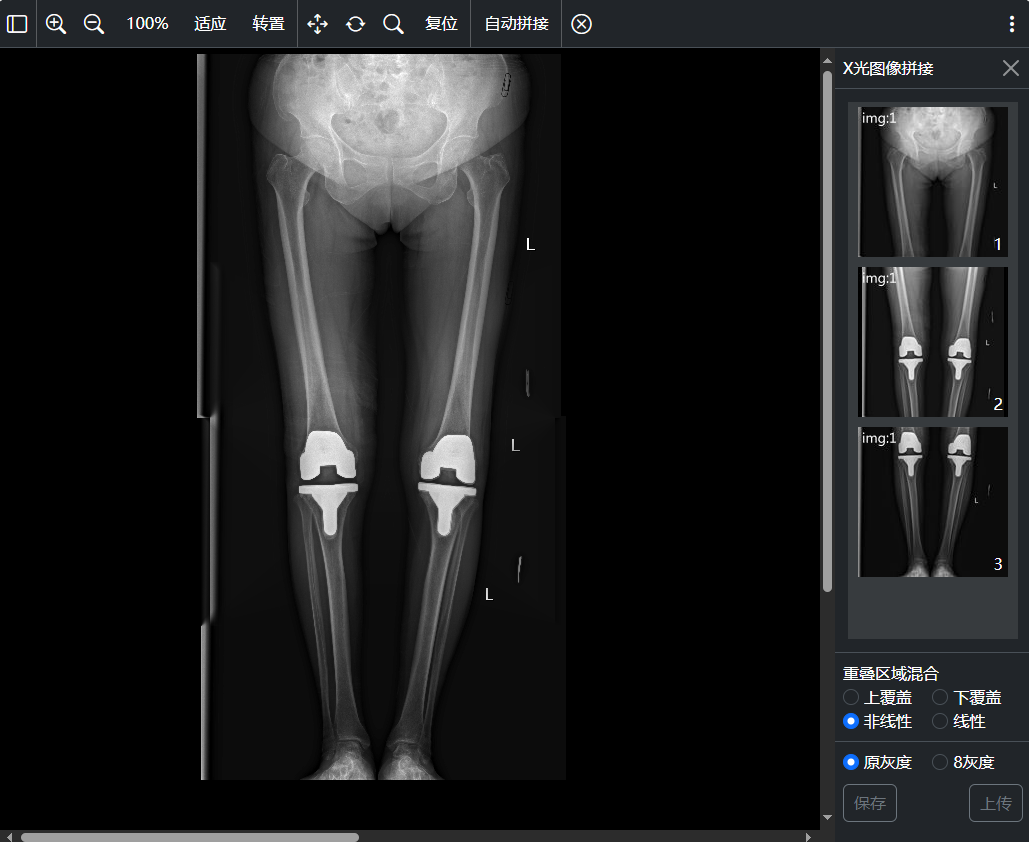

其它: PR(GSPS灰度一致性显示)加载管理、KO加载管理、SR结构化报告浏览、MPEG视频DICOM浏览、支持DICOM Shutter显示、支持DICOM Overlay图层显示、MG乳腺自动悬片显示、用户自定义图像处理、X光长骨拼接等;

十一、X光图像 拼接

X光图像拼接窗口: 支持自动拼接、手工拼接、拼接图像保存、拼接图像上传功能;支持触发拼接图片上传完成事件